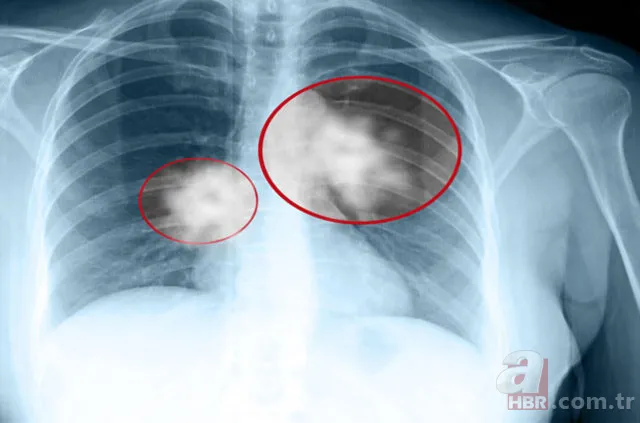

Erkeklerde en sık görülen kanser türü olan akciğer kanseri, kanserden ölüm nedenleri arasında birinci sırada yer alıyor.

Günümüzde kanser vakalarına bakıldığında kalın bağırsak, meme ve prostat kanseri nedeniyle yaşamını yitirenlerin toplamından daha fazla kişi akciğer kanseri nedeniyle hayatını kaybediyor.